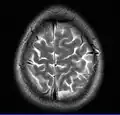

Normal axial T2-weighted MR image of the brain

Normal axial T2-weighted MR image of the brain -